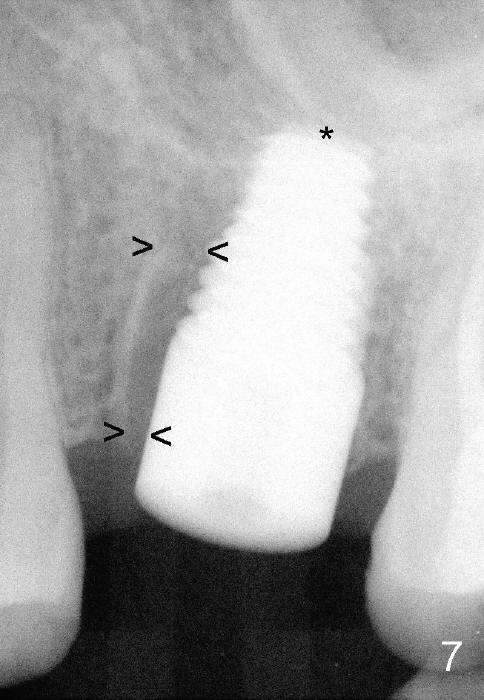

Fig.6 shows 4.5 mm tap in place with stability. It appears too high. When it is removed, the sinus membrane is found to have been perforated. The next taps (5,6 and 7 mm) are placed shorter by 3 mm with stability. A piece of collagen dressing and a small amount of bone graft (Fig.7 *) are inserted to the osteotomy before placement of a 7x14 mm implant.

Fig.8 illustrates the implant (blue) placed in the middle of the socket. The remaining buccal and lingual gaps (black) are then closed by graft and membrane. Placing the graft in the deeper portion of the mesiobuccal socket is not so easy because the large implant blocks the entrance (Fig.7 between lower arrowheads). If more graft has been dispensed and the earlier PA shows larger upper space exists (Fig.6 between upper arrowheads), the graft should be placed to that region prior to implant placement.

Twenty-one months postop, the patient returns for #15 RCT. PAs show that although there is a narrow space in the original mesial socket (Fig.9 *), the 1st thread space is partially obliterated with the bone (<). In contrast, the distal 1st thread space is completely obliterated (Fig.10 >). After the RCT, impression is taken for #14 and 15. Although there is no sign of periimplantitis, the 7x14 mm implant looks too large for the site with possible buccal thread exposure 4 years 9 months post cementation (Fig.11). To reduce complications, a much small fixture will be at #30.